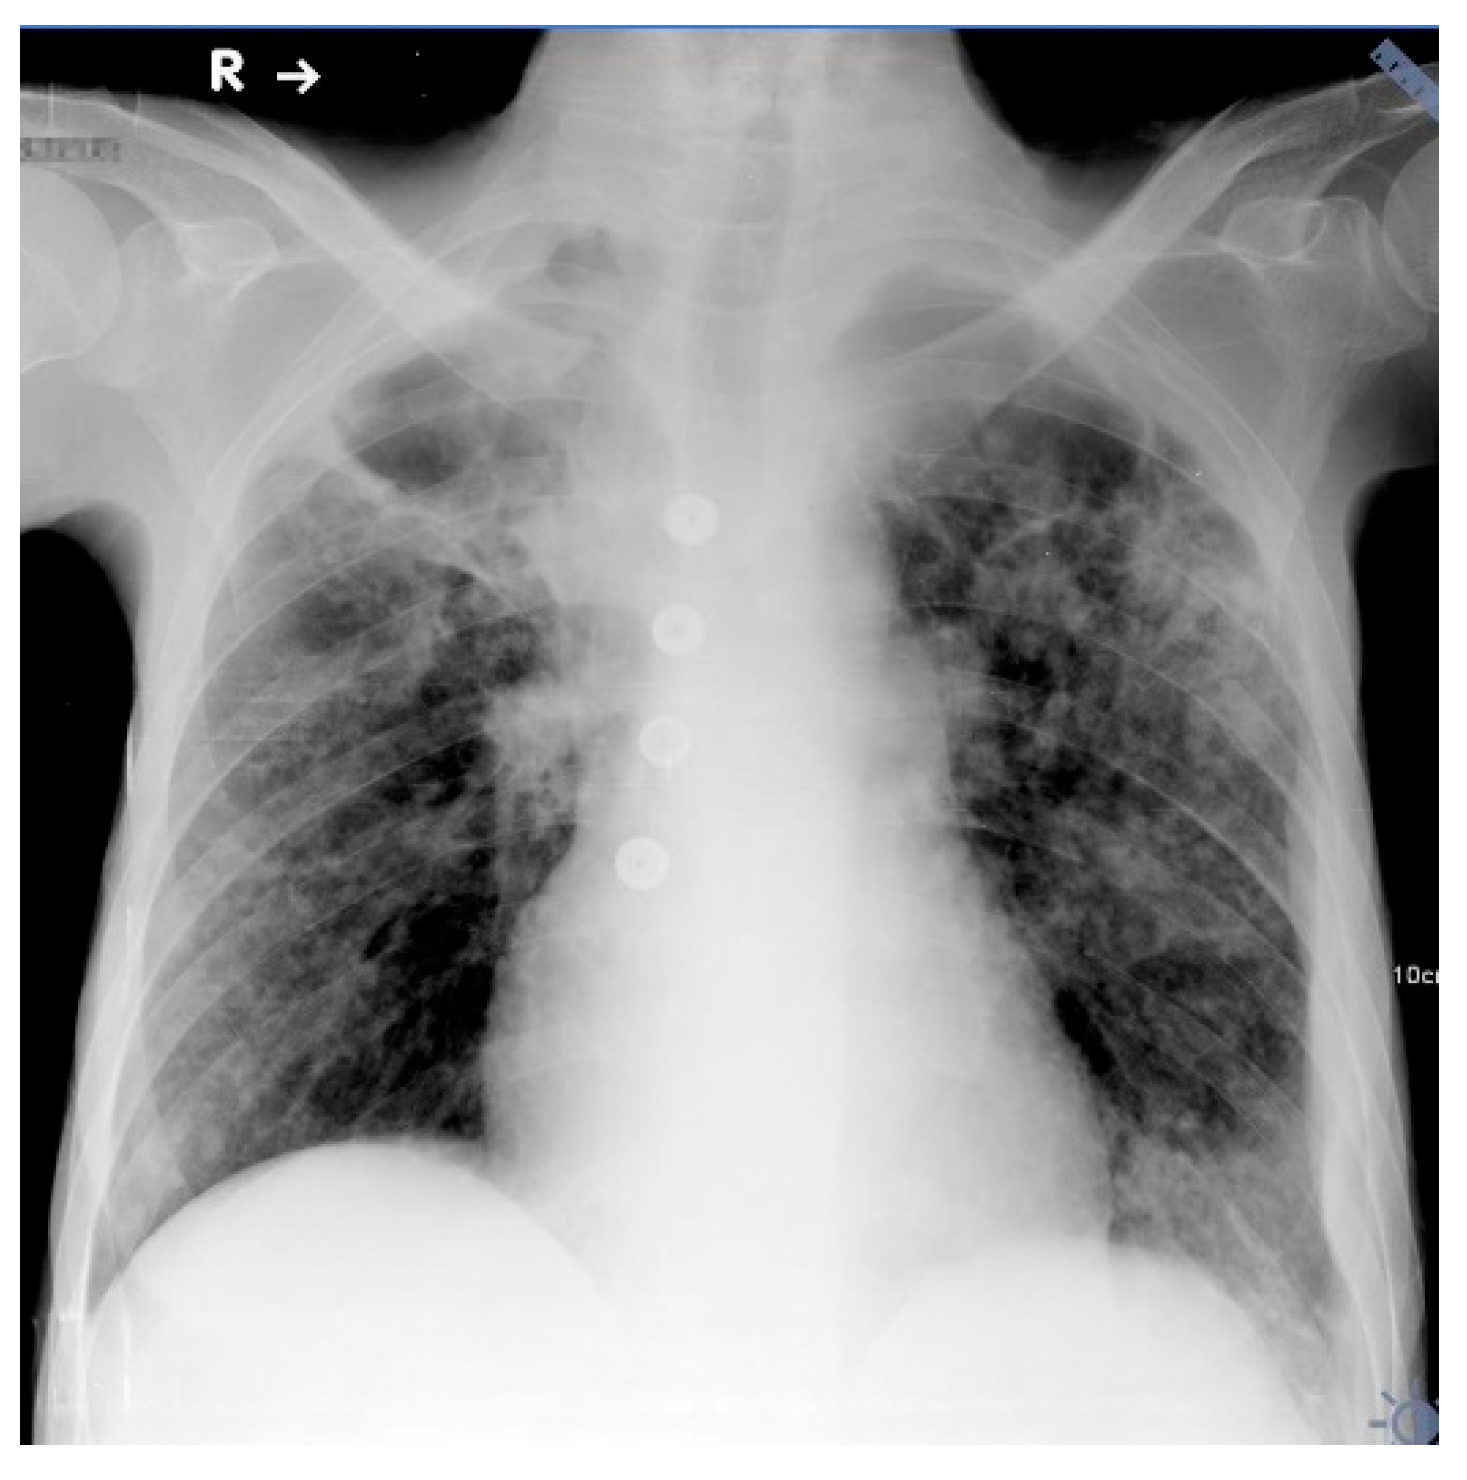

The chest radiograph showed extensive, parenchymal consolidations in both lungs, with low-attenuation areas in upper zones suggesting cavitations (Figure 2).

Figure 2.

Chest X-ray anteroposterior in a horizontal position. Extensive, parenchymal consolidations in both lungs with low-attenuation areas in upper zones suggest cavitations.